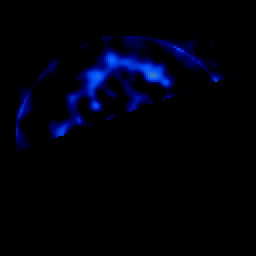

SPECT TL Study #4 -- Slice #47

[Home][Help][Clinical][Tour 1][Tour 2][Tour 3] Slice 47